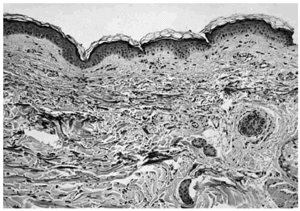

Se realizaron asimismo biopsias de la piel sana inmediatamente contigua a las lesiones. Las tinciones para fibras elásticas evidenciaron la desaparición de las mismas en la dermis papilar y su conservación en la dermis reticular (fig. 5).

Fig. 5.--Piel sana perilesional (paciente 1). Desaparición de las fibras elásticas elaunina y oxitalán en la dermis papilar (tinción fibras elásticas ×100).